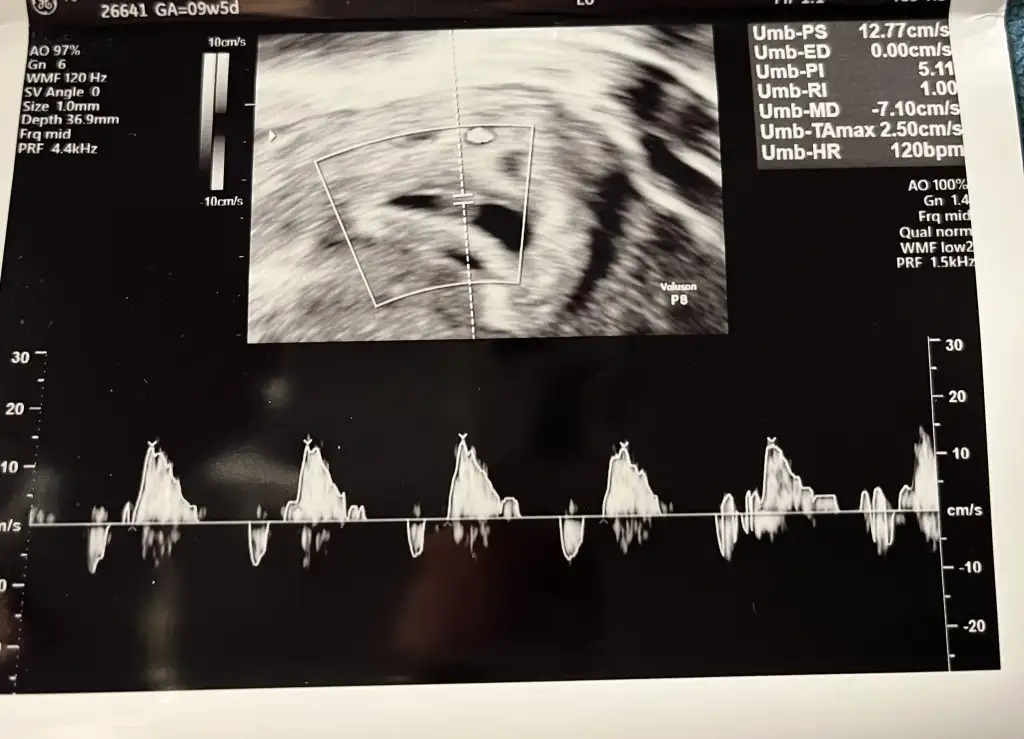

Kuzum bi kızçe gibi hissettim tabi bildiğimden değil sadece hissiyatKızlarrr hadi bana da tahmin yapın ay7 haftalığız şu an ve vajinal ultrason bu

Kesenin aşağısına ya da sağa yapışık oluyormuş kızlar..Tahmin yapan bir üyenin yorumunu gördüm..Kızlarrr hadi bana da tahmin yapın ay7 haftalığız şu an ve vajinal ultrason bu

Vajinalda ayna yansıması olmuyor...Bebek sizin sol üstte gözüküyor anladığım kadarıyla..O zaman bu teoriye göre erkek diyorum ben![]()